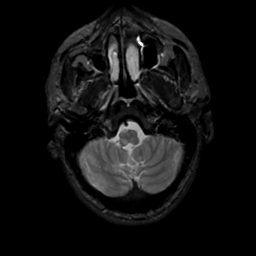

MR Study #10, April 28, 1991 -- Slice #7

[Home][Help][Clinical][Tour 1][Tour 2] Slice 7